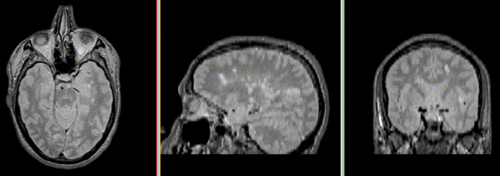

Slicer Registration Library Case 04: Multi-contrast brain MRI of Multiple Sclerosis

this is the main fixed reference image. All images are ev. aligned into this space this is the main fixed reference image. All images are ev. aligned into this space lleft this is the intra-subject moving image.

exam 1: PD exam 1: T2 exam 1: T1-Gd

this is the inter-subject moving image, but also the reference for exam 2 this is the inter-subject moving image, but also the reference for exam 2 lleft this is the moving image.

exam 2: PD exam 2: T2 exam 2: T1-Gd

This scenario occurs in many forms whenever we wish to assess change in a series of multi-contrast MRI. The follow-up scan(s) are to be aligned with the baseline, but also the different series within each exam need to be co-registered, since the subject may have moved between acquisitions. Hence we have a set of nested registrations. This particular exam features a dual echo scan (PD/T2), where the two structural scans are aligned by default. The post-contrast T1-GdDTPA scan however is not necessarily aligned with the dual echo. Also the post-contrast scan is taken with a clipped field of view (FOV) and a lower axial resolution, with 4mm slices and a 1mm gap (which we treat here as a de facto 5mm slice). read more about this dataset here

• reference/fixed : PD.1 baseline exam , 0.9375 x 0.9375 x 3 mm voxel size, axial acquisition, RAS orientation.

• fixed T2.1 baseline exam , 0.9375 x 0.9375 x 3 mm voxel size, axial acquisition, RAS orientation. -> (aligned with PD.1, not used for registering)

• moving: T1.1 (GdDTPA contrast-enhanced scan) baseline exam 0.9375 x 0.9375 x 5 mm voxel size, axial acquisition.

• moving: PD.2 follow-up exam 0.9375 x 0.9375 x 3 mm voxel size, axial acquisition.

• moving: T2.2 follow-up exam 0.9375 x 0.9375 x 3 mm voxel size, axial acquisition. -> same orientation as PD2, will have same transform applied

• moving:T1.2-GdDTPA follow-up exam0.9375 x 0.9375 x 5 mm voxel size, axial acquisition. -> undergoes 2 transforms: first to PD.2, then to PD.1